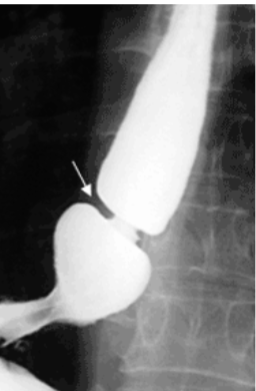

Achalasia

Failure of LES to relax (open) after swallowing + lack of coordinated esophageal peristalsis

Due to selective degeneration or damage to the parasympathetic post-ganglionic neurons that relax the lower sphincter & are responsible for peristalsis

Primary: Idiopathic (most common); incidence ↑ with age

Secondary: Acquired: Chagas Disease (T. Cruzi), Diabetic Autonomic Neuropathy, Amyloidosis, Cancer

Triple-A (Achalasia-Addisonianism-Alacrima)/Allgrove syndrome: Achalasia, Adrenal insufficiency & lack of tear production

Dysphagia to solids & liquids, regurgitation of undigested food, chest pain, aspiration pneumonia

Cancer risk for both esophageal Squamous & Adenocarcinoma

Beak sign on Barium swallow with mega-esophagus